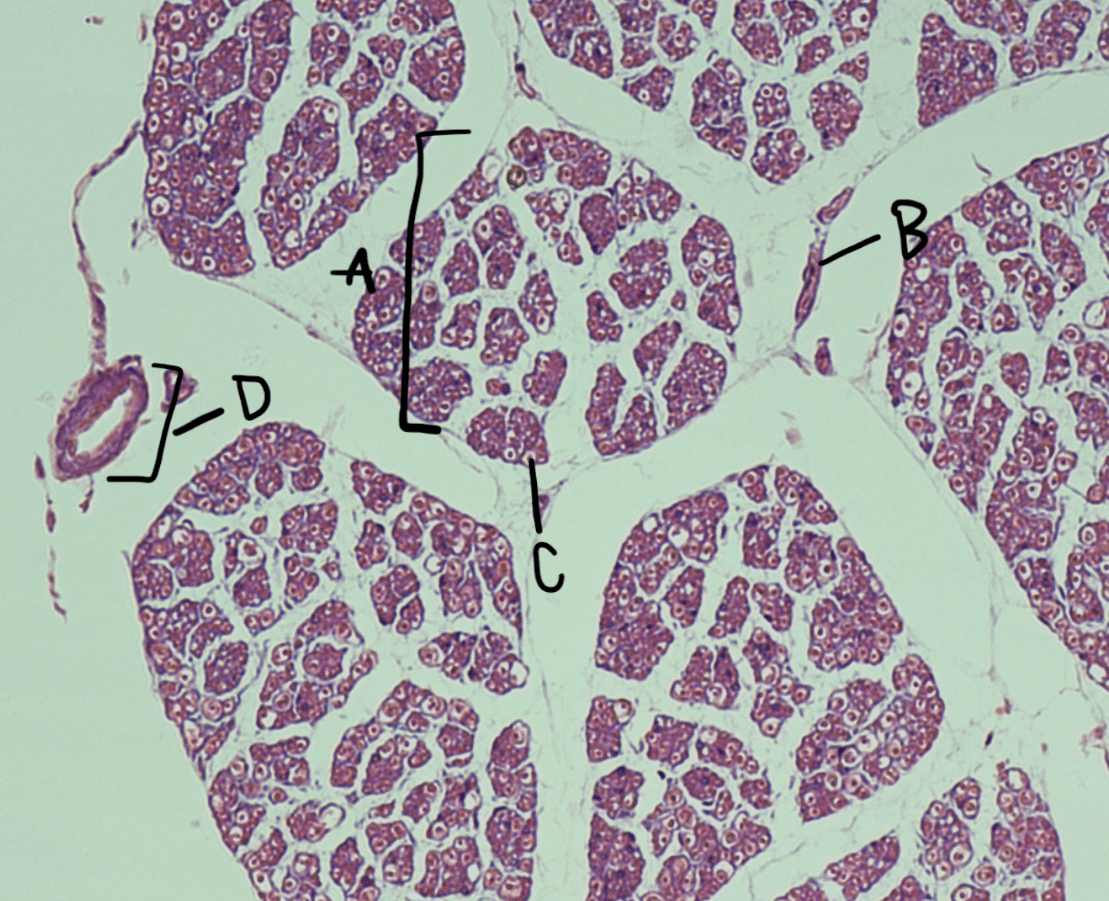

Label A, B, C, D.

A: Nerve fascicle

B: Perineurium

C: Myelinated axon

D: Blood vessel